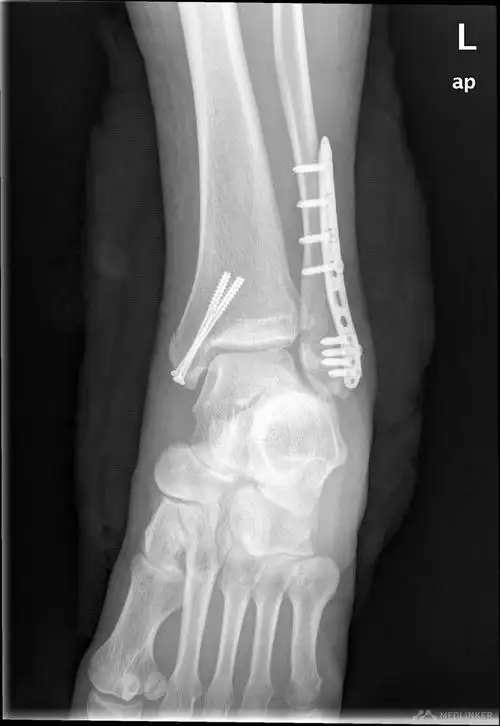

左三踝骨折